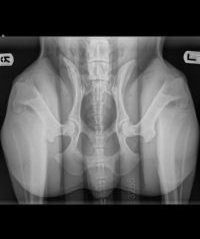

Heupdysplasie

Heupdysplasie is een pijnlijke gewrichtsaandoening van de heupen. We zien heupdysplasie voornamelijk bij de grotere hondenrassen maar ook bij kleinere honden kan het voorkomen.

Als een hond heupdysplasie heeft, past de heupkop niet goed in de heupkom of zit deze te los. Hierdoor kan de heupkop geheel of gedeeltelijk uit de kom schieten. Het eruit schieten doet pijn. De kans op artrose van de heupen neemt toe naarmate de heupkop minder strak in de kom zit. Dus hoe meer speling in het heupgewricht, hoe groter de kans op artrose. Op oudere leeftijd kan deze artrose voor pijnklachten zorgen.